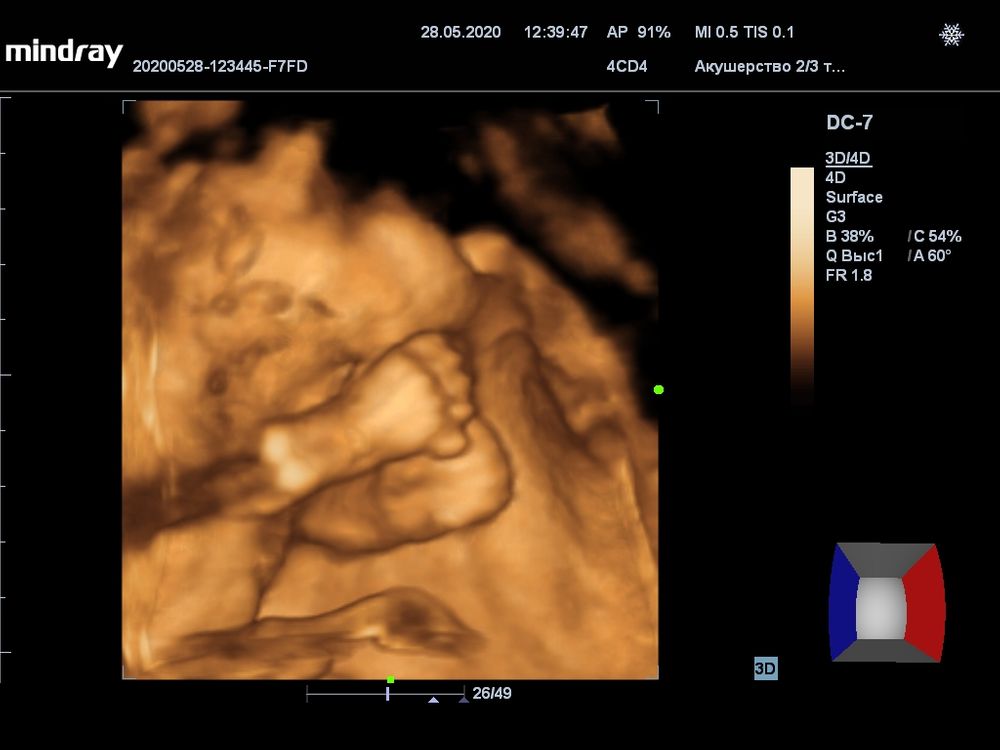

Сходили с мужем, довольные, хоть и сын лежит в тазовом и вокруг лица руки да ноги. Врач действительно опытная, меня вертели, как шашлык на мангале и паре кадров удалось снять 🤣👌🏻 На счет тазового не парюсь, потому что он еще триста раз изменит позу, места и времени у него вагон и маленькая тележка ☺️ Фоток конечно отдали кипу, с аппарата узи 12 штук и еще в цветной распечатке на принтере 6 штук))

Как я мечтала о таких фото😍Но сын ни показал ни причинное место,ни лицо😂Неопределенного пола был😂Вот все,что мне досталось))

ⓙⓤⓛⓔⓣⓣⓐツ, пятки в монитор))) за то самый сладкие пятки)